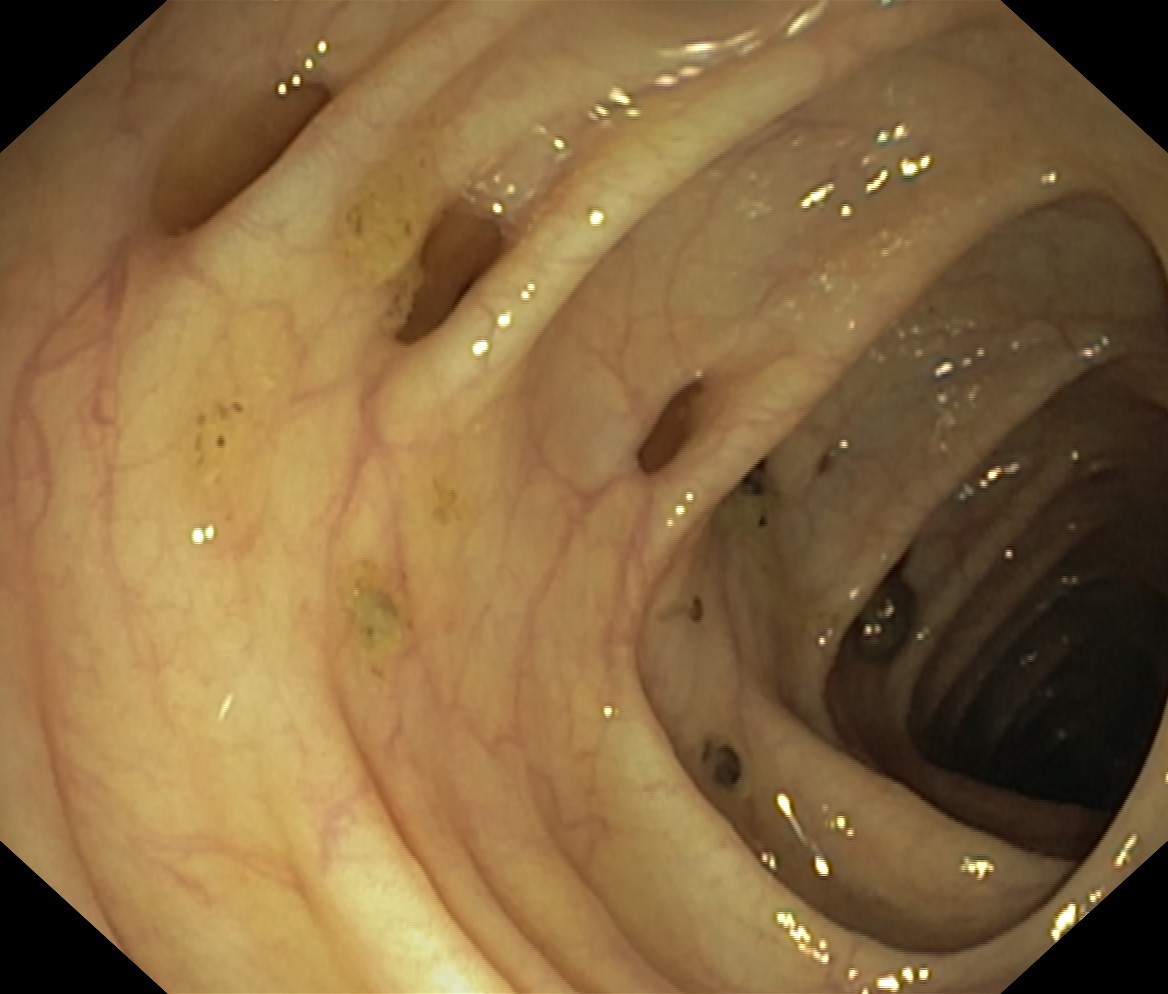

Uchyłki